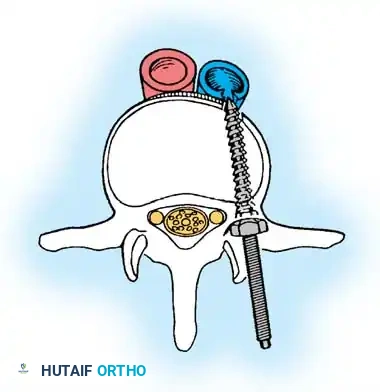

PRINCIPLES OF POSTERIOR SPINAL ARTHRODESIS

The ultimate goal of scoliosis surgery is not merely instrumentation, but a solid, lifelong arthrodesis. The classic extra-articular Hibbs technique has largely been abandoned in favor of comprehensive intra-articular fusion techniques that incorporate the facet joints.

The success of a spinal arthrodesis relies on a delicate interplay of factors:

1. Surgical Preparation: Meticulous removal of all avascular soft tissue and thorough decortication of the posterior elements.

2. Biomechanical Stability: Rigid segmental instrumentation to neutralize micromotion.

3. Biological Environment: Adequate delivery of osteoprogenitor cells and a vascularized graft bed.

4. Host Factors: Optimization of patient nutrition and strict cessation of smoking, as nicotine is a potent inhibitor of osteogenesis and significantly increases pseudarthrosis rates.

Biomechanics of Bone Grafting

Bone graft incorporates most effectively under compressive loads and is biologically disadvantaged in environments of distraction. Therefore, in scoliosis correction, if autogenous bone is limited, it should be preferentially concentrated on the concave side of the curve, which is subjected to compressive forces, rather than the convex side, which experiences tension. Furthermore, the farther the fusion mass is placed from the instantaneous axis of rotation, the more effectively it will neutralize movement across that axis.